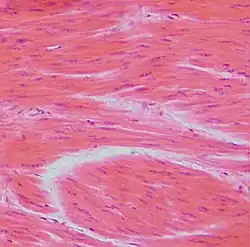

Tkanka mięśniowa gładka (łac. textus muscularis glaber) – tkanka mięśniowa składająca się z wrzecionowatych komórek, zawierających jedno centralnie położone jądro komórkowe[1]. Filamenty są w niej ułożone nieregularnie (brak prążkowania). Działa ona niezależnie od woli, powolnie i długotrwale, jest odporna na zmęczenie.

Ten typ tkanki znajduje się między innymi w ścianach przewodów, na przykład układu pokarmowego, dróg oddechowych, pęcherza moczowego, dróg rodnych. Tkanka mięśniowa gładka pełni funkcje żywotne, na przykład nadaje kształt soczewkom, poszerza źrenice, reguluje przepływ krwi przez naczynka krwionośne, przesuwa pokarm w układzie pokarmowym. Bardzo ważna jest jej odporność na znużenie, czyli zdolność do pozostawiania w długotrwałym skurczu, nawet w warunkach niedoboru tlenu.